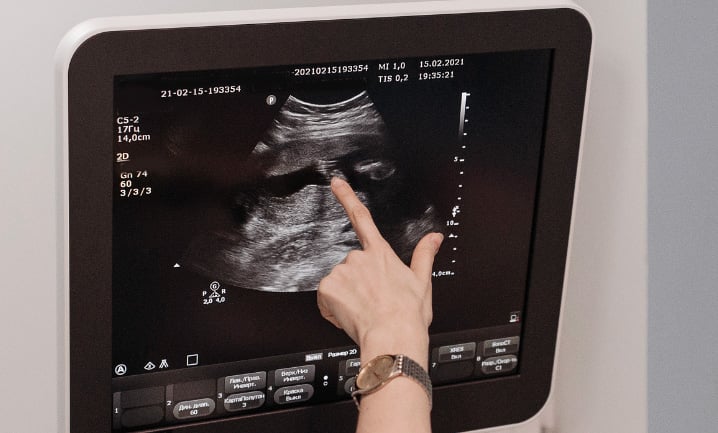

Les organes génitaux de bébé commencent à se développer dès le début de grossesse, cependant ils ne sont pas visibles immédiatement. L’échographie du premier trimestre, aussi appelée « échographie de datation » a lieu entre la 11e et la 13e semaine d’aménorrhée. Elle a pour objectif d’estimer la date d’accouchement, de vérifier le bon fonctionnement du cœur de bébé et de dépister d’éventuelles anomalies.

L’échographie du deuxième trimestre ou « échographie morphologique » se déroule entre la 20e et la 24e semaine d’aménorrhée. Lors de cet examen, le radiologue mesure précisément le fœtus pour s’assurer que sa croissance est normale. C’est à ce moment-là que la détermination du sexe du bébé devient particulièrement fiable, car les organes génitaux sont désormais suffisamment développés pour être visibles à l’écran. Néanmoins, il arrive que le fœtus « se cache » et soit dans une position qui rend l’observation difficile. Pour certains parents, il faut alors s’armer de patience et attendre l’échographie du troisième trimestre pour espérer un angle de vue plus favorable et enfin connaitre le sexe de leur bébé !

L’échographie 3D est une technique d’imagerie médicale qui fournit des clichés plus détaillés et particulièrement réalistes de bébé. Elle peut donc faciliter l’identification de ses organes génitaux. Cependant, l’examen en 3D n’a aucun caractère obligatoire et n’apporte pas forcément un diagnostic plus précis que les échographies 2D réalisées par un médecin ou un gynécologue expérimenté. L’échographie 3D est parfois préconisée dans le suivi d’anomalies de grossesse. Elle peut aussi être volontairement plébiscitée par les futurs parents pour mieux visualiser leur enfant grâce à des images plus nettes. Pour certains d’entre eux, cela rend la parentalité plus concrète et permet de créer un premier lien affectif avec leur bébé.